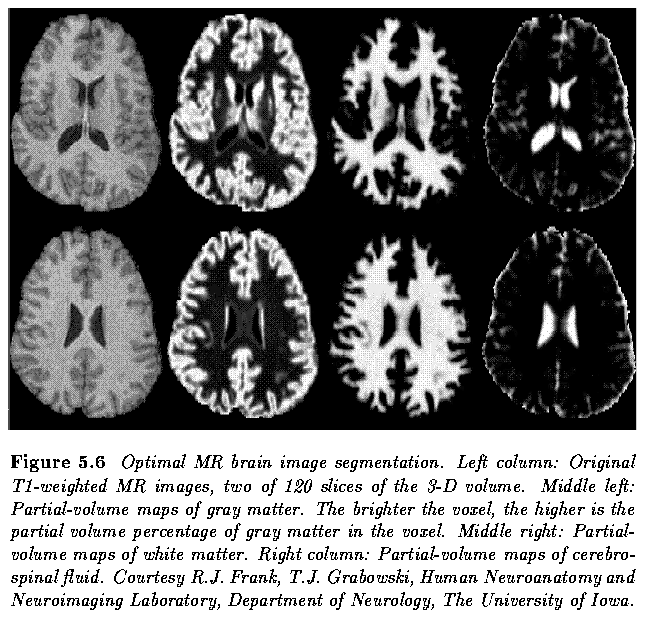

Example - Brain MR image segmentation

- A combination of optimal and adaptive thresholding

- determines optimal gray level segmentation parameters in local subregions for which local histograms are constructed

- gray-level distributions corresponding to n individual (possibly non-contiguous) regions are fitted to each local histogram that is modeled as a sum of n Gaussian distributions so that the difference between the modeled and the actual histograms is minimized